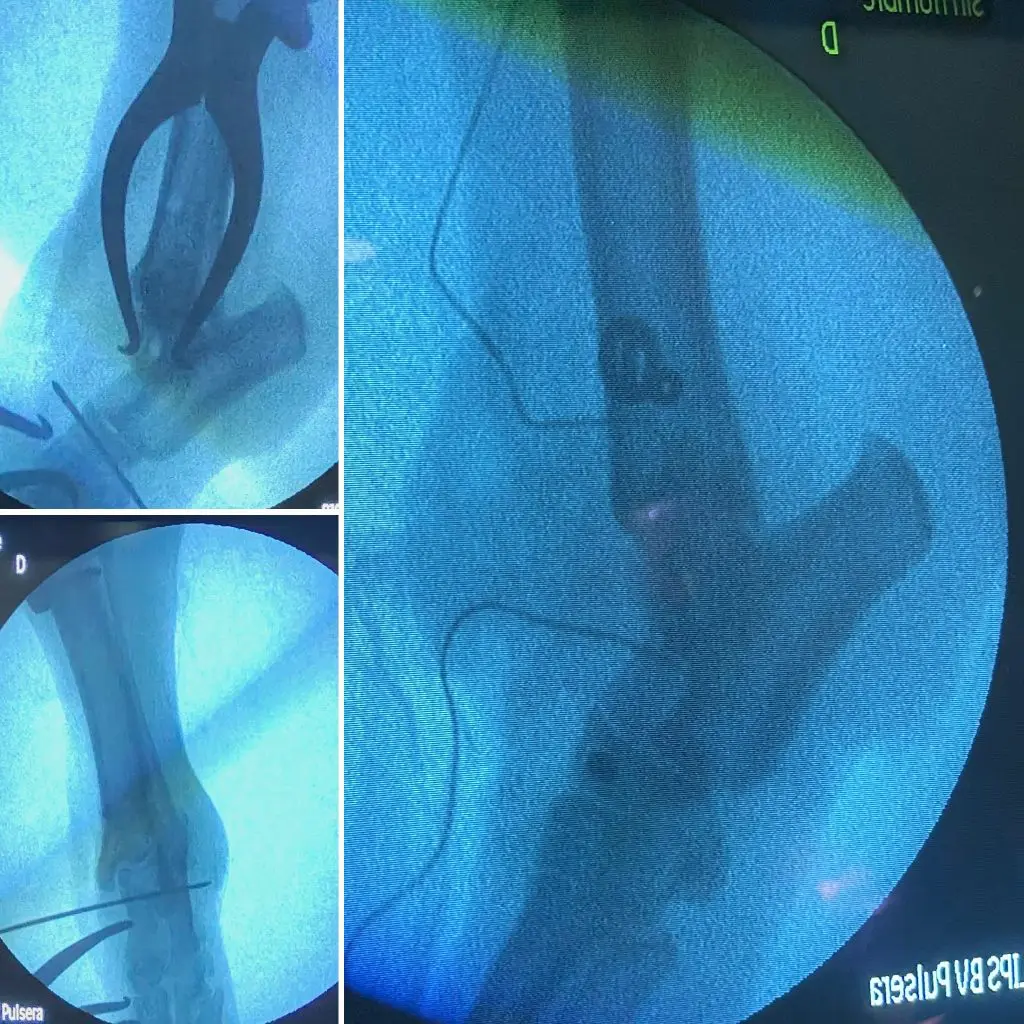

Con el fin de ejecutar los túneles y colocar los tornillos de una manera precisa, empleamos un fluoroscopio para verificar intraquirúrgicamente su disposición.

Al finalizar el procedimiento y cerrar el abordaje quirúrgico por planos, comprobamos radiológicamente la correcta ubicación de los implantes, así como la estabilidad definitiva de la articulación, tanto en flexión como en extensión.